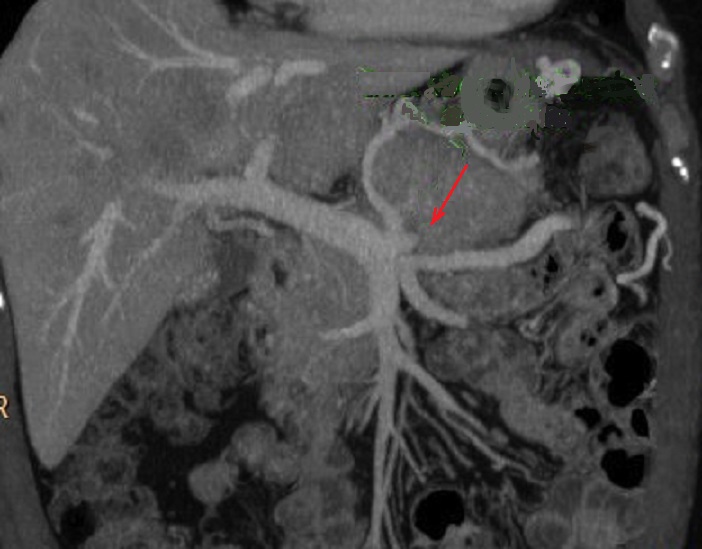

Image radiologique

d'un tumeur endocrine non fontionelle du queue

pancreas a grand taille . Ce que entraine une

deformation neoplasique du systeme veine splenique .

Image vde engainement veineuse et abrution

neoplasique de veine splenique ( fleche rouge c) |